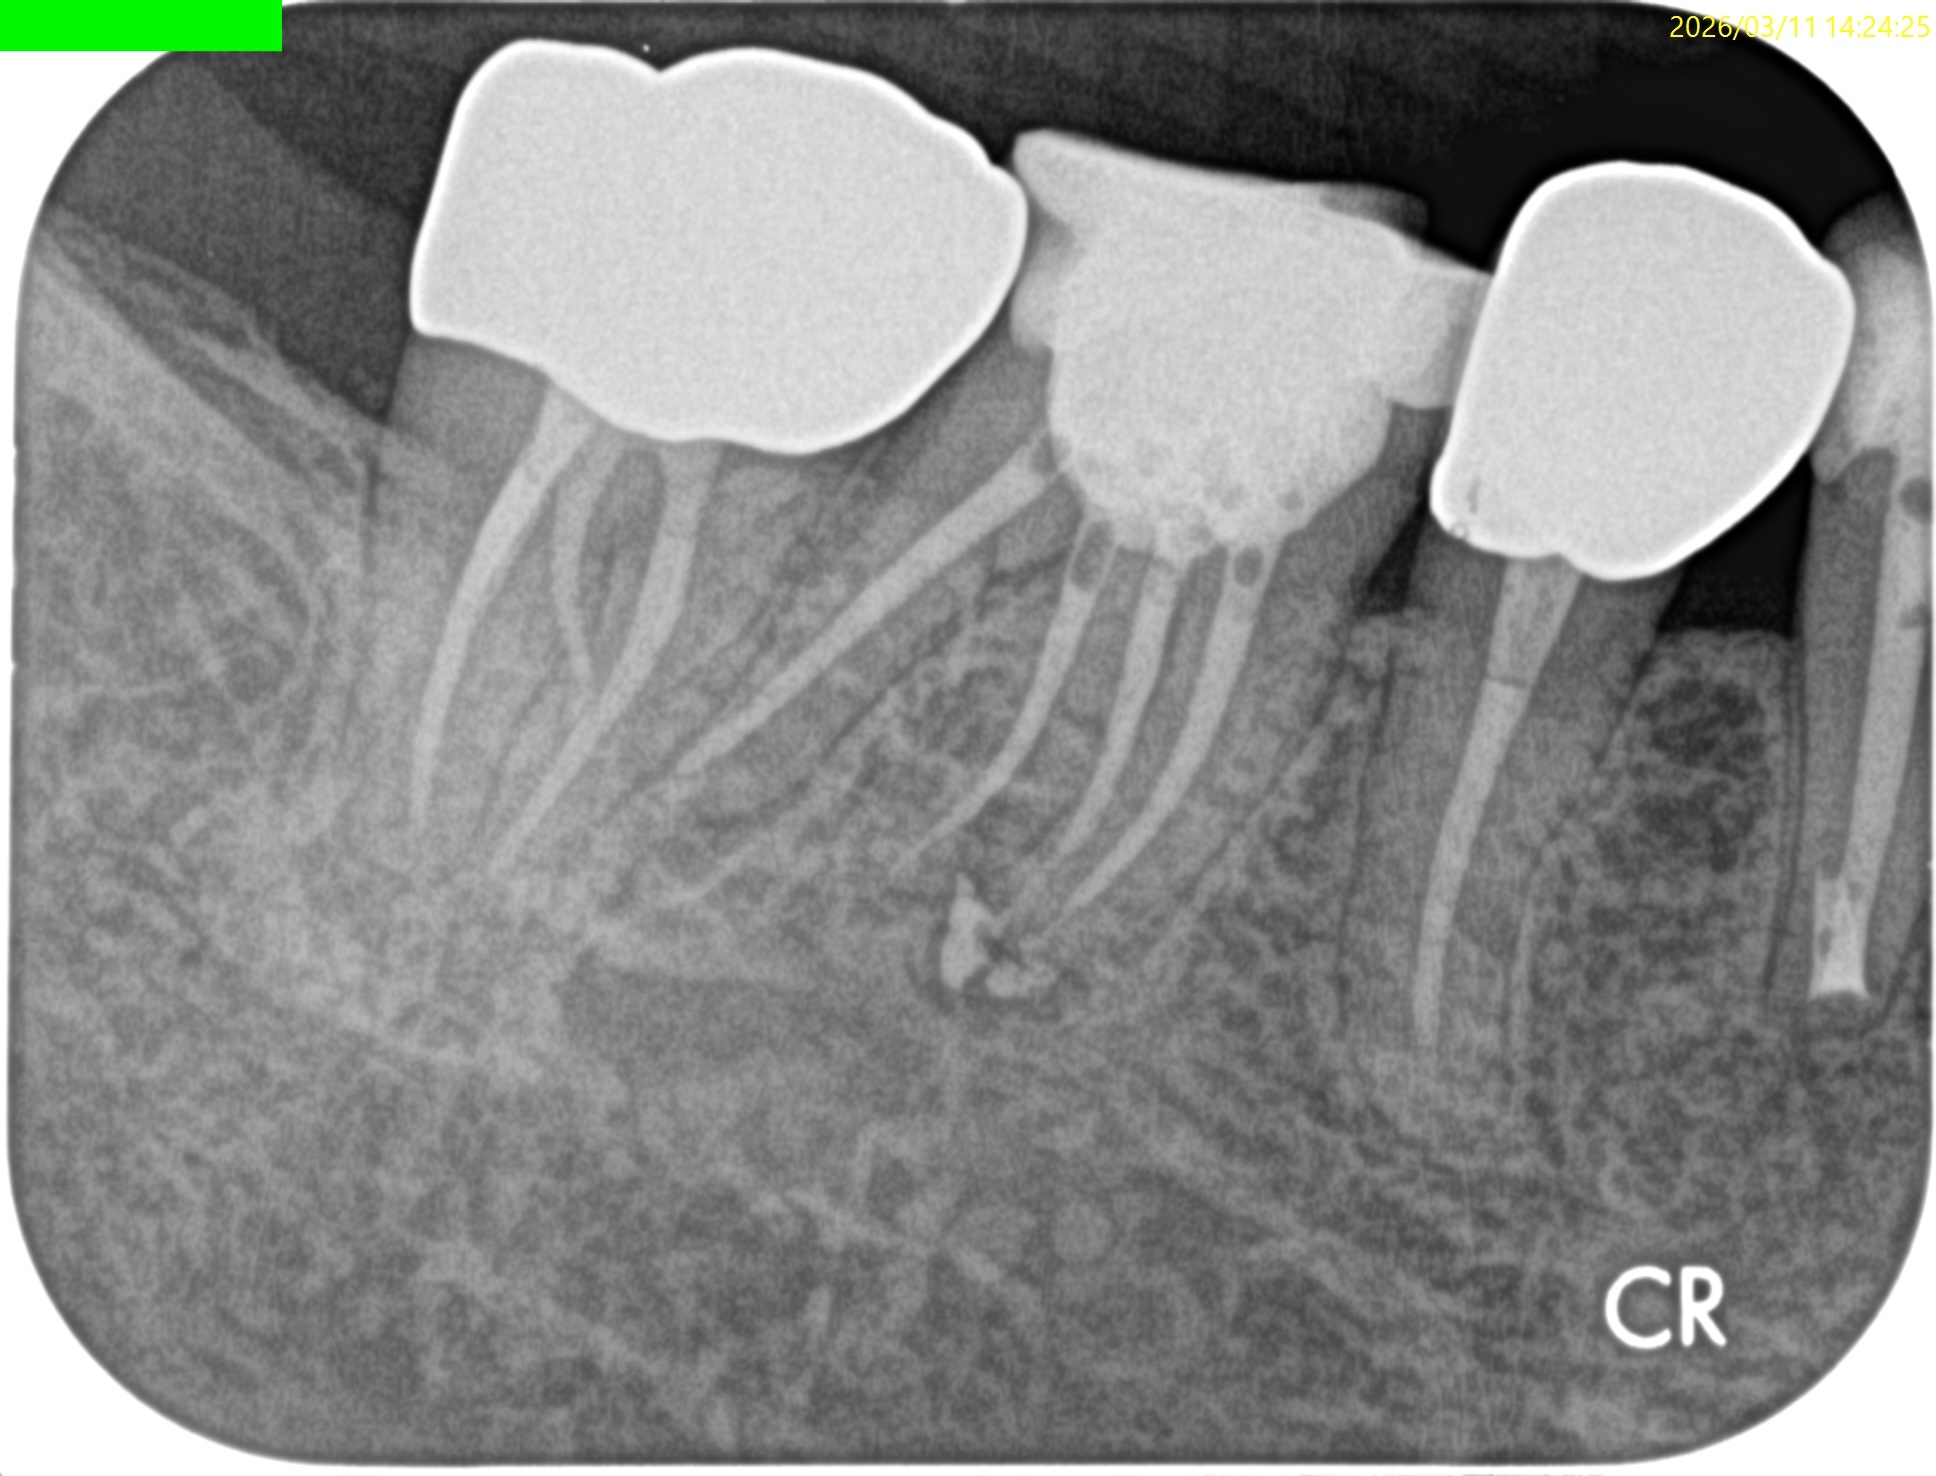

術後にPA, CBCTを撮影した。

MB

ML

D

Radix

ということで問題ないだろう。